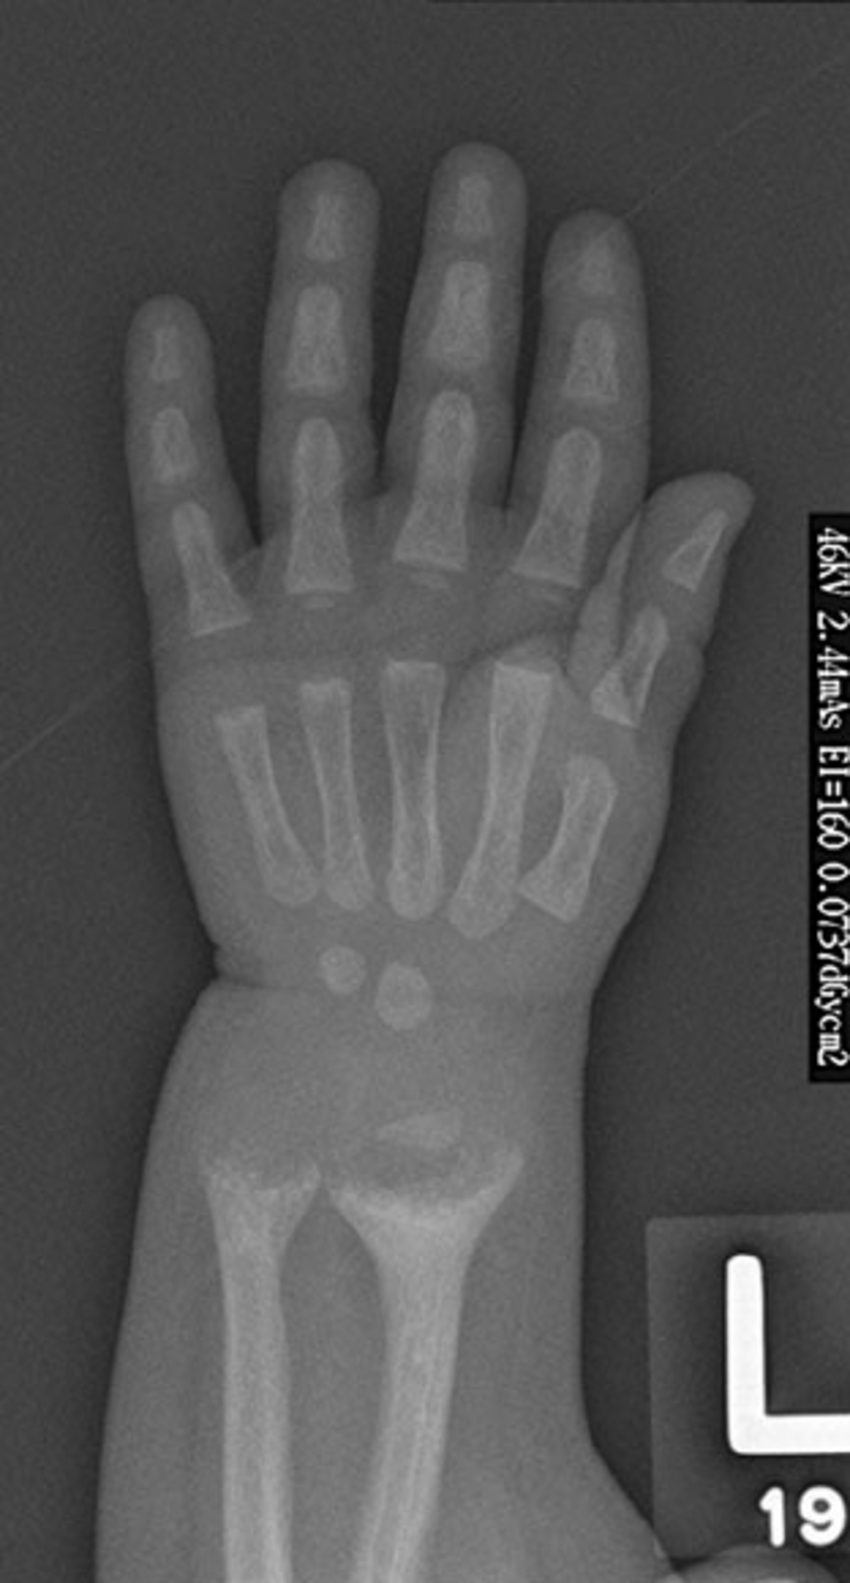

Wrist widening is a common finding in individuals with severe malnutrition. It is attributed to deficiency of vitamin D. Reference: https://www.ncbi.nlm.nih.gov/pmc/articles/PMC5763407/ Image via: https://www.researchgate.net/figure/Classic-rachitic-changes-at-the-wrist-cupping-fraying-and-widening-resulting-in-the_fig1_51563666